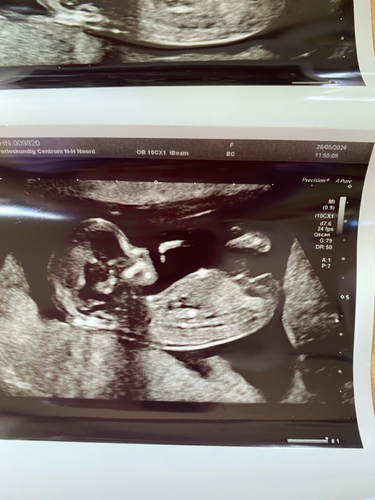

🩵🩷😍?

Ik denk een meisje maar niet heel duidelijk . 🩷

Ik heb hier nog een fotootje, maar ook vaag. Bedankt iig!🥰